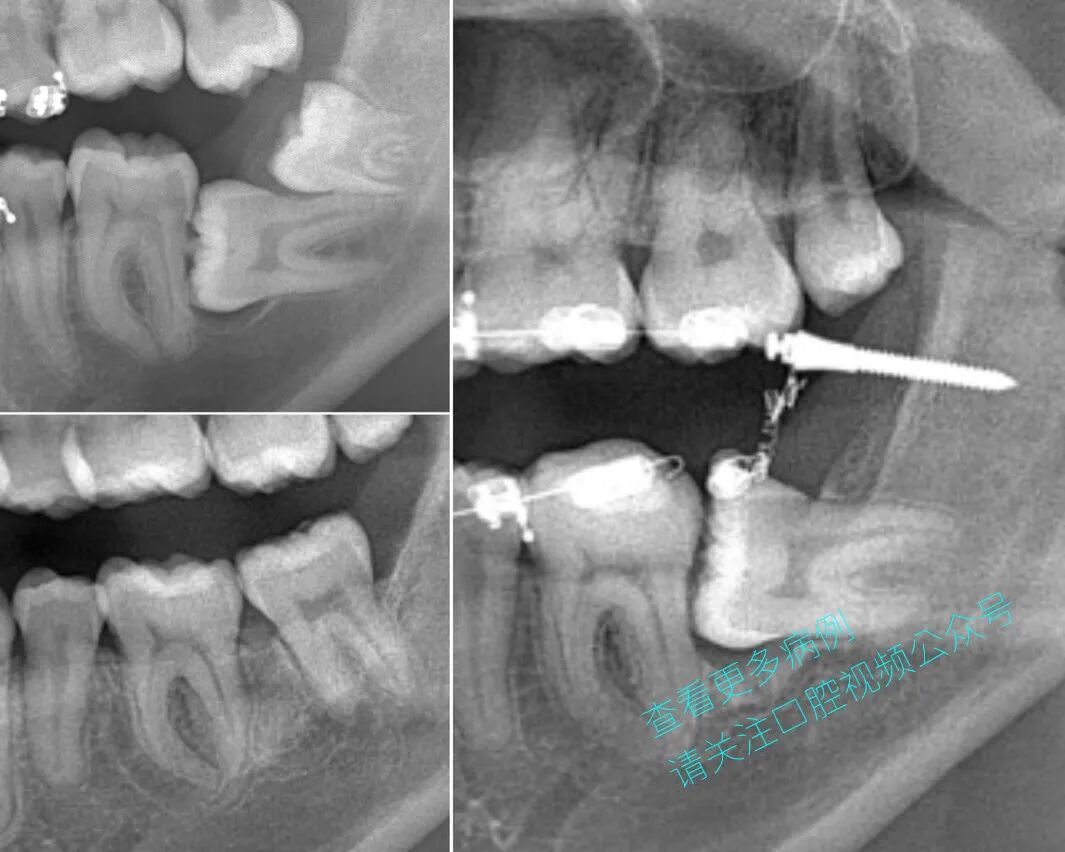

患者为18岁男性,既往接受过正畸治疗。37号牙水平阻生,紧贴36号牙。

手术拔除了38号牙,并在下颌升支植入一枚2×14 mm微型种植体,用于牵引并使37号牙平行移动。